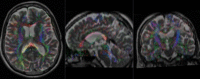

Registration Results

![]() |

baseline & T2 before registration |

baseline to T2 after affine+nonrigid alignment |

| DTI and T2 before & after registration |